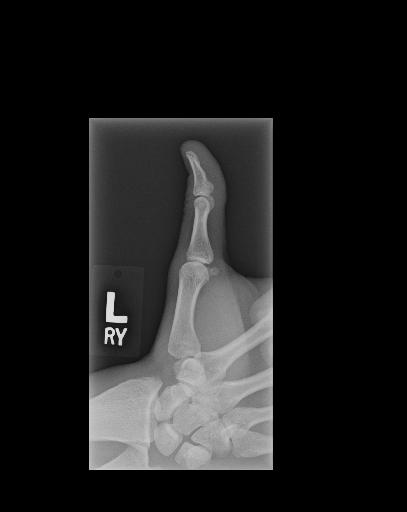

In this work, we focus on a subset of the MURA dataset [17] containing only hand images. In total, we have 5,543 images of 2,018 studies of 1,945 patients. Each study is labeled as negative or positive, where positive means that there was an anomaly diagnosed in this study. There are 521 positive studies, with a total of 1,484 images. Figure 1 shows some examples from the dataset. In summary, our contributions are as follows:

The first step in our pipeline is to detect the X-ray image carrier in the image. To this end, we apply OpenCV’s contour detection using Otsu binarization [14], and retrieve the minimum size bounding box, which does not need to be axis-aligned. This works sufficiently well as long as the majority of the image carrier is within the image (cf. Figure 3). However, the approach might fail for heavily tilted images or those where larger parts of the image carrier reach beyond the image border.

Hand Localization

To further improve the detection of hands, and in particular split the images where two hands are depicted on one image, we manually labeled approximately 150 bounding boxes in the images. Using this small dataset, we fine-tune a pre-trained single shot multibox detector (SSD) [12] with MobileNet as taken from TensorFlow. An exemplary results can be seen in Figure 3.